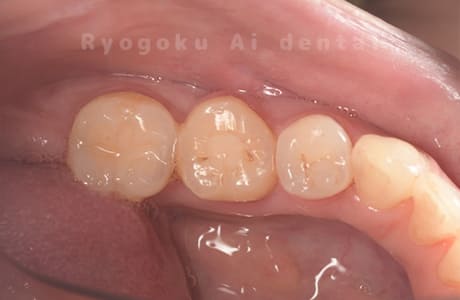

他院で右下の根の治療を行い、セラミックを被せる説明をされていたが、根の治療が終わらないため転院された患者さんです。隣の親知らずの抜歯の必要性と、根の治療を行なっている歯牙の予後が悪いため、移植治療を提案し、右下の親知らずの抜歯と同時に、右下の奥歯(7番)への移植治療を行いました。被せ物を行う必要もなく、順調に経過してます。